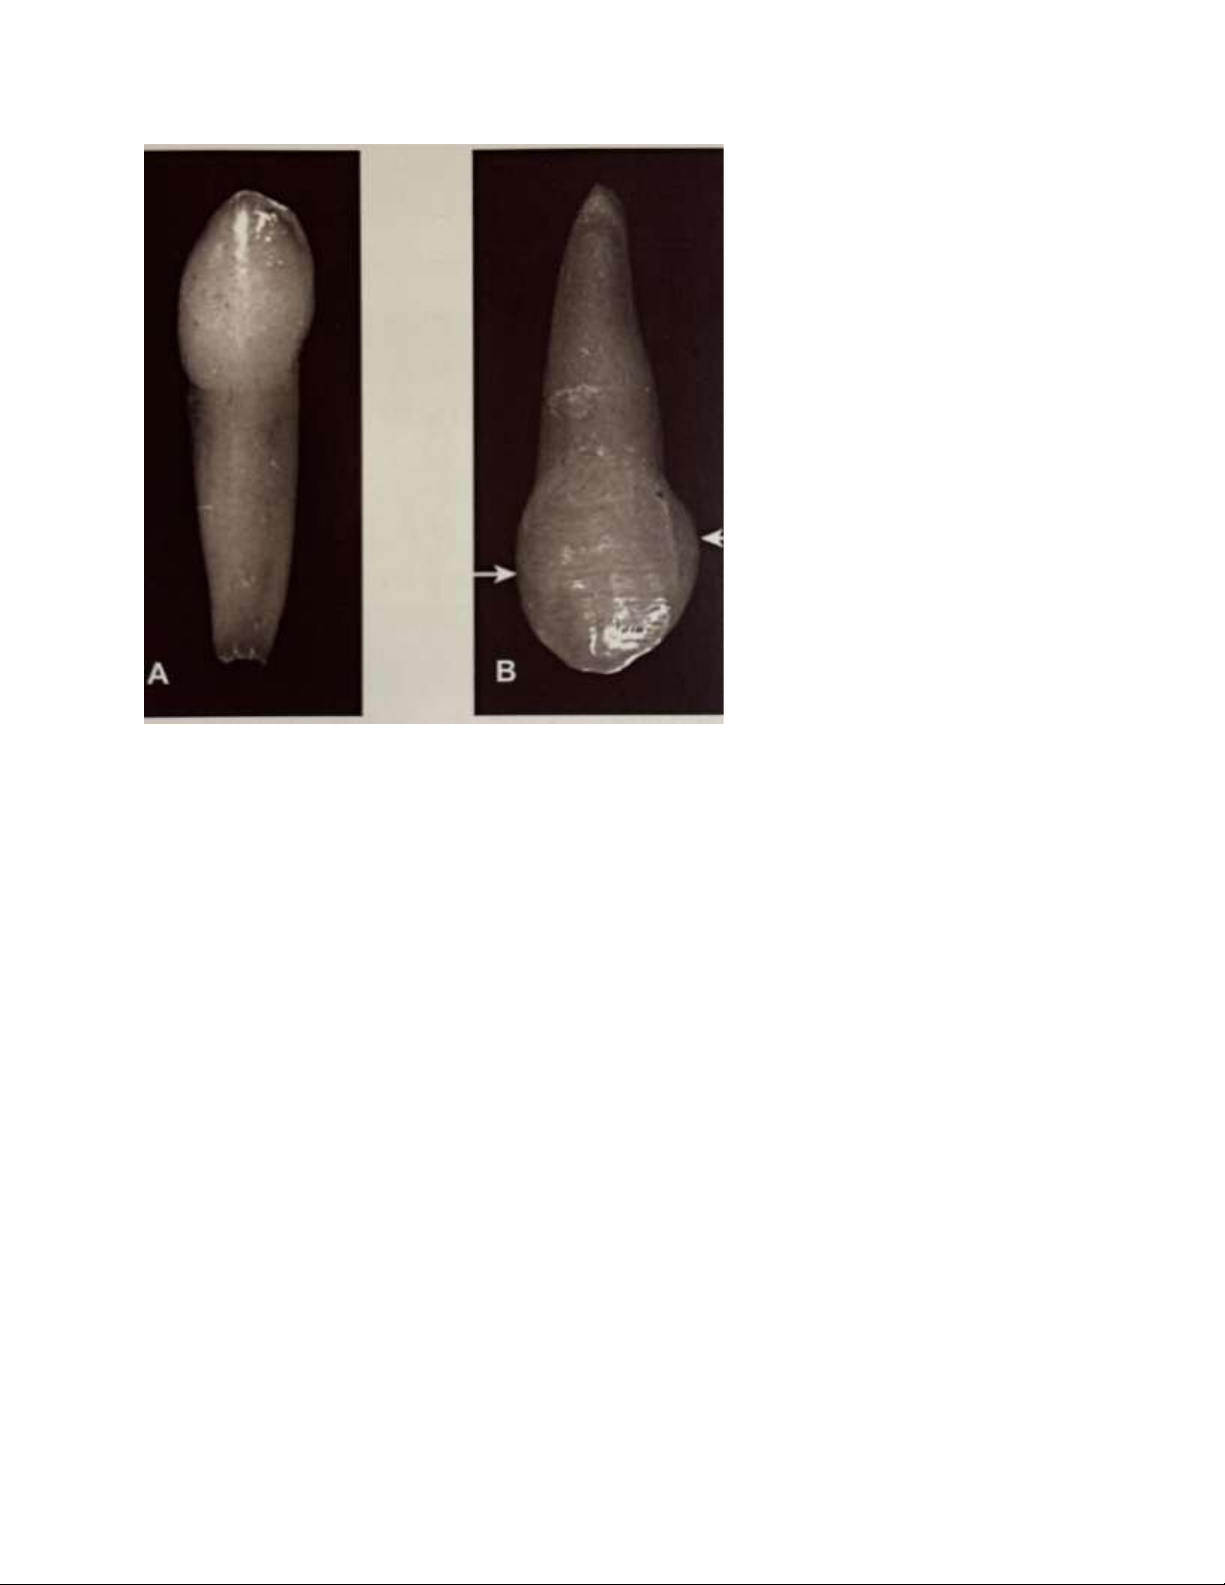

Hình 9. Răng nanh sữa nhìn từ mặt ngoài

A. Răng nanh sữa dưới, với thân hẹp chiều gần xa, mủi nhọn.

B. Răng nanh sữa trên với gờ mái gần dài hơn gờ múi xa, tiếp xúc bên xa gần phía cắn hơn.